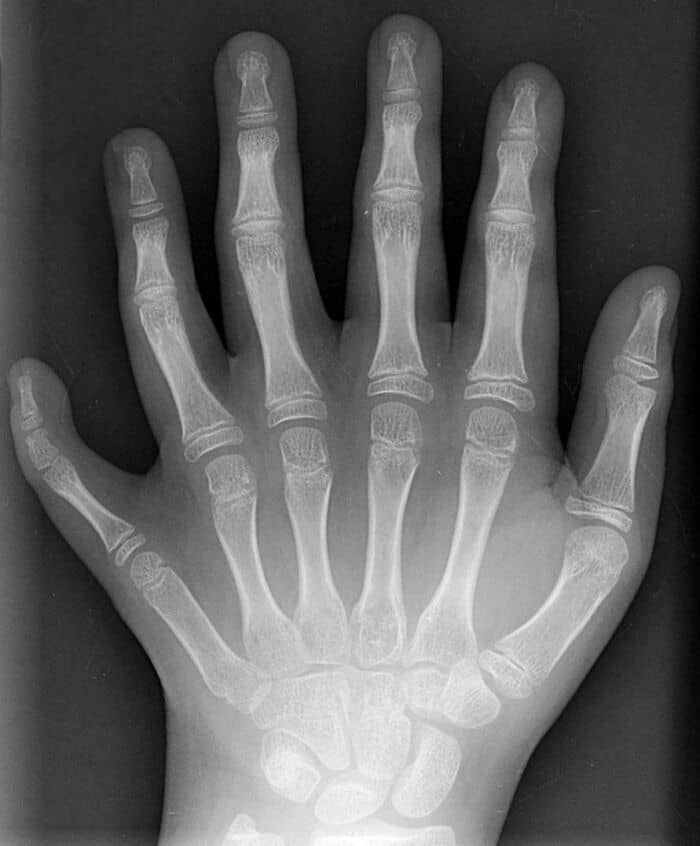

#53 An X-Ray Of A Hand With Six Fingers

#23 This Condition Is Called Mirror Hand Syndrome, Less Than 100 Cases Have Ever Been Diagnosed And The Cause Is Still Unknown